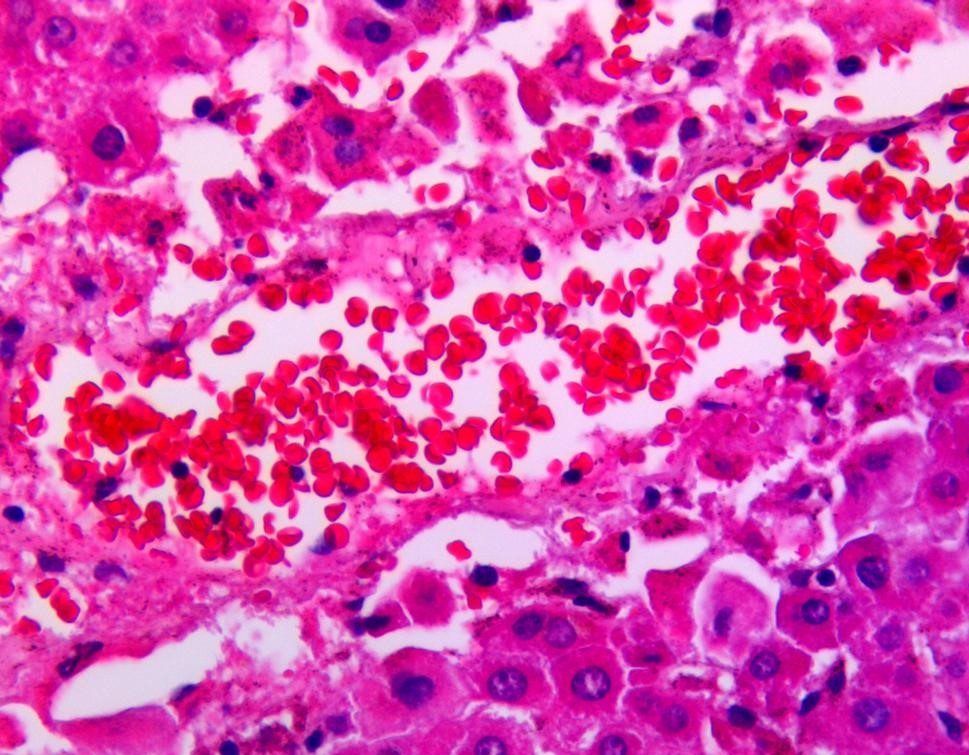

H&E STAINS

top